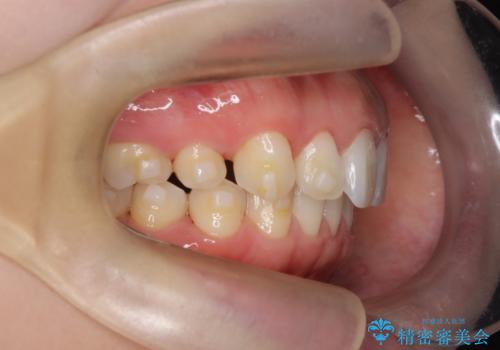

- 患者様は、上下顎の歯列不正と前歯部の突出感を主訴としてご来院されました。診断の結果、上顎左右第一小臼歯を抜歯することでスペースを確保し、歯列全体を整える方針としました。本来はワイヤー矯正が推奨されるケースですが、患者様のご希望により、透明なマウスピース型矯正装置「インビザライン」を使用した治療計画を立案しました。治療期間は約3年で、奥歯の噛み合わせを維持しながら、徐々に前歯の位置を整えました。